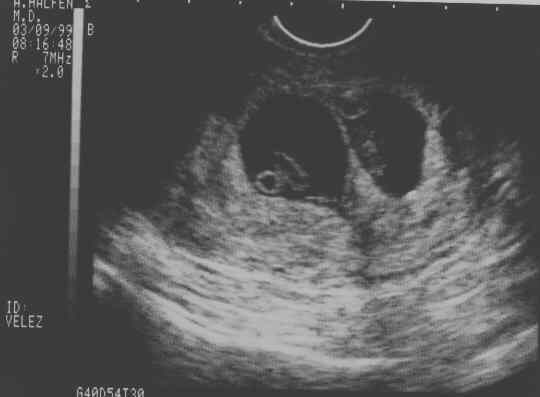

V-Twins

eggs2.JPG - 19.8 K eggs3.JPG - 22.4 K eggs4.JPG - 11.7 K babies-1a.JPG - 21.3 K